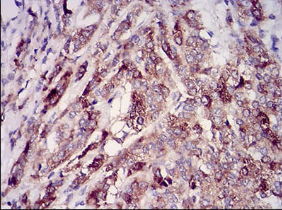

RAB27A Mouse Monoclonal antibody[7D7C9]

IHC    1/200 - 1/1000